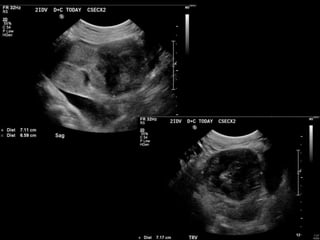

HISTORY

• 40 yo female 8.5 weeks pregant

• S/P D&C for pregnancy implanted at site of

c-section scar

• 6 weeks post D&C patient presents with

heavy persistent bleeding

• For Pelvic US

• HCG = 451 mIU/mL

• What are the findings?

• What is the differential diagnosis?

• What are your recommendations?

• What is the diagnosis?

• What is the treatment?